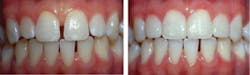

Direct bonded veneers before (left) and after.